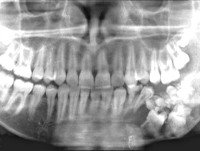

Для диагностики одонтомы, в первую очередь, используются данные клинического осмотра пациента. Для уточнения диагноза обязательно проводится рентгенологическое исследование (ортопантомограмма, КТ челюсти), на котором выявляется ограниченная гомогенная тень. Также используется гистологическое исследование для исключения озлокачествления опухоли.

Одонтома. Это доброкачественная опухоль из элементов зубных тканей, которая развивается в костях челюстей. Симптомы одонтомы зависят от места локализации опухоли, ее размеров и выраженности воспалительных явлений в окружающих тканях. Чаще всего одонтома развивается безболезненно и характеризуется медленным ростом. Такая опухоль выявляется врачом-стоматологом случайно при рентгенографии или при удалении зуба. В некоторых случаях одонтома прорастает в костную ткань, и тогда в полости рта образуется язва, нередко сопровождающаяся формированием гнойных свищей. Рентгенологические и гистологические методы исследования позволяют дифференцировать опухоль. Лечение одонтом - хирургическое.